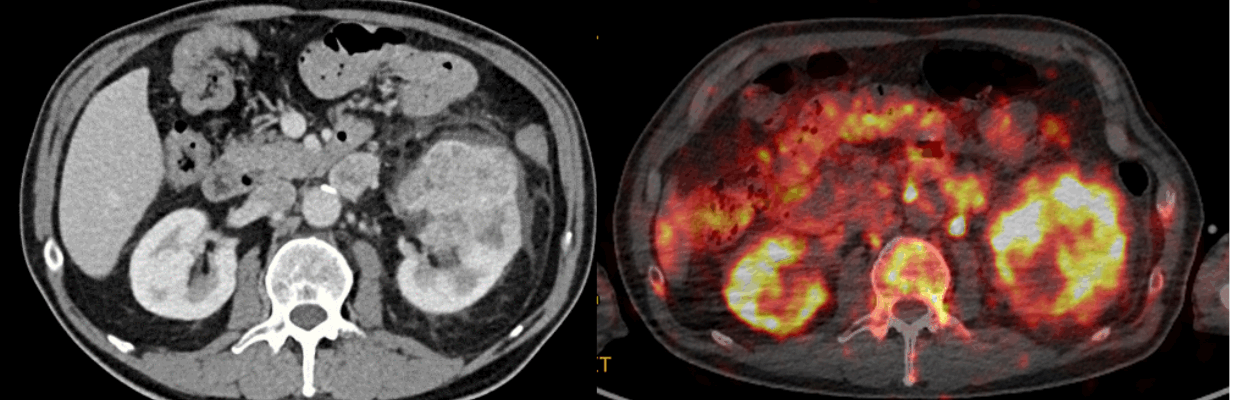

The trial, called iPREDICT, uses an investigational imaging agent called CD8 ImmunoPET which illuminates CD8+ cells on a PET scan.

CD8+ cells have been shown to attack and kill cancer cells and where they are located may indicate how well a patient responds to immunotherapy – a treatment which uses the immune system to find and attack cancer cells.

Currently, the only way to determine the number of CD8+ cells is by biopsy, but this only provides information on a single tumour lesion. CD8 ImmunoPET could provide important information on these cancer-killing cells in the body.